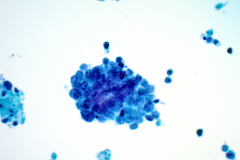

BSCC reportedly display very high nuclear/cytoplasmic ratio with coarse chromatin, inconspicuous to prominent nucleoli and nuclear pleomorphism. The nuclei also mold, and the cells tend to arrange in cohesive clusters, with necrosis in the background.6 This case demonstrates all these criteria (see figures 1-4).